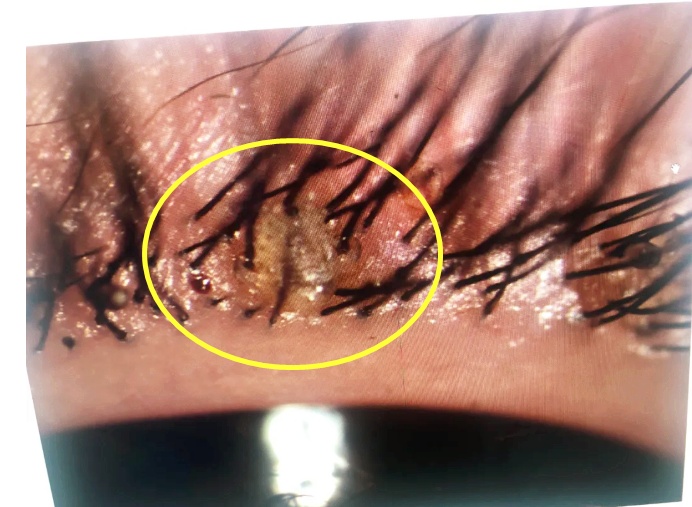

“睫毛根部沾满了胶水,结膜充血发红、肿胀,再仔细检查发现,有一根粗硬的假睫毛附着左眼上睑板的凹沟中。”所幸就诊及时,掉落的假睫毛没有进一步磨损角膜,否则眼睛可能会遭受更严重的损伤。

裂隙灯显微镜下照片显示睫毛根部(睑缘)充血、沾满了胶水 医院供图